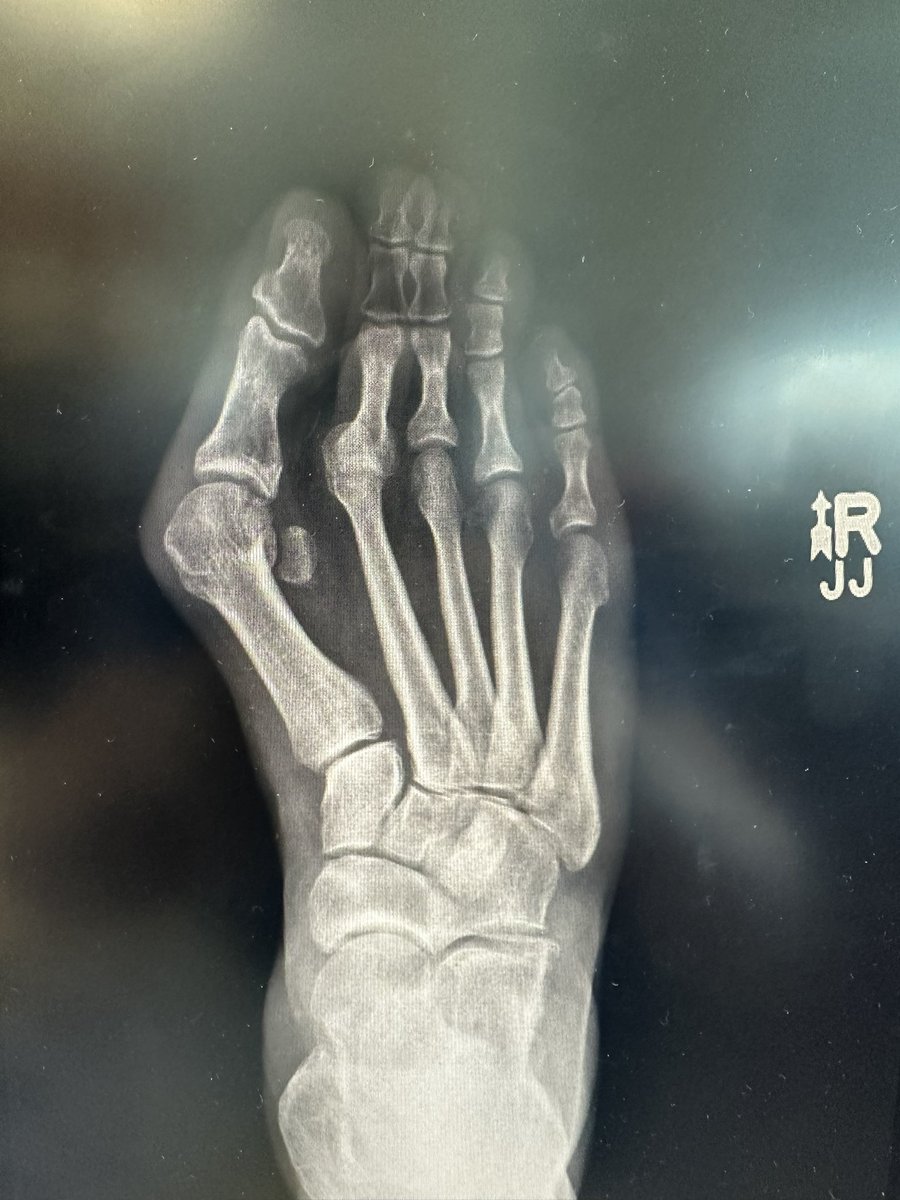

Virginia Beach Orthopedic Foot and Ankle Surgeon